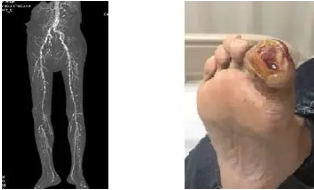

透析患者下肢血管钙化      糖尿病足

尿毒症患者更易罹患足部感染和糖尿病足,发病危险增加10倍。严重的糖尿病足并发难以控制的感染、骨髓炎时截肢不可避免。国外报道透析患者约有10%进行了截肢,每年约有4%的透析患者需要进行截肢术。50%~60%的透析患者存在外周血管和神经病变,与糖尿病高发、下肢血管病变严重、免疫功能低下、低白蛋白血症、足趾脂肪垫缺失局部压力增加等有关。

北京清华长庚医院肾内科(通讯员 李敏侠)我国目前有近50万透析患者,因糖尿病或钙磷代谢紊乱,下肢血管病变并足部感染的患者越来越多。数据显示15%的透析患者存在外周血管病变,慢性肾脏病患者外周血管病变是非慢性肾脏病患者的2.5倍,与糖尿病、糖尿病肾病患者增加,外周血管钙化,慢性炎症反应等有关。